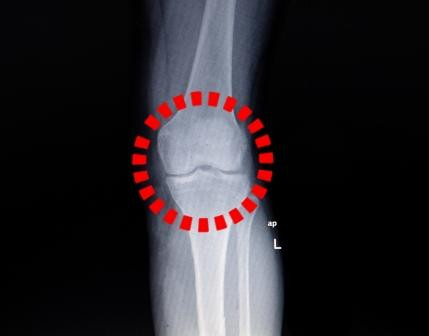

Bij een trauma van de knie is het verleidelijk om de anamnese af te raffelen en over te gaan naar het lichamelijk onderzoek. Maar hoe betrouwbaar zijn anamnese en onderzoek om bijvoorbeeld een voorste kruisbandruptuur (VKB) vast te stellen? En kan de huisarts dat net zo goed als de orthopeed?